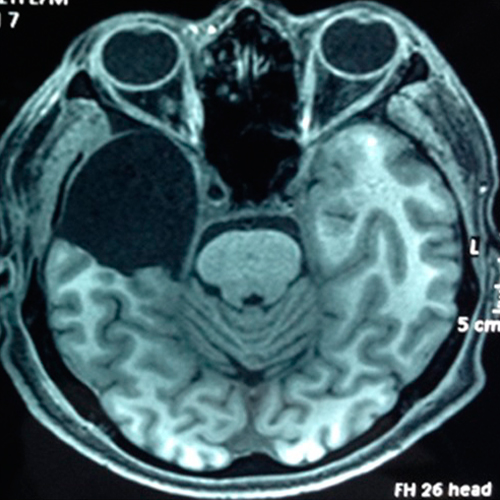

• Hemisferectomía funcionales:

• Indicado en síndromes hemisféricos como encefalitis de Rasmussen, hemimegancefalia, síndrome de Sturge Weber, alteraciones de la migración neuronal, etc.